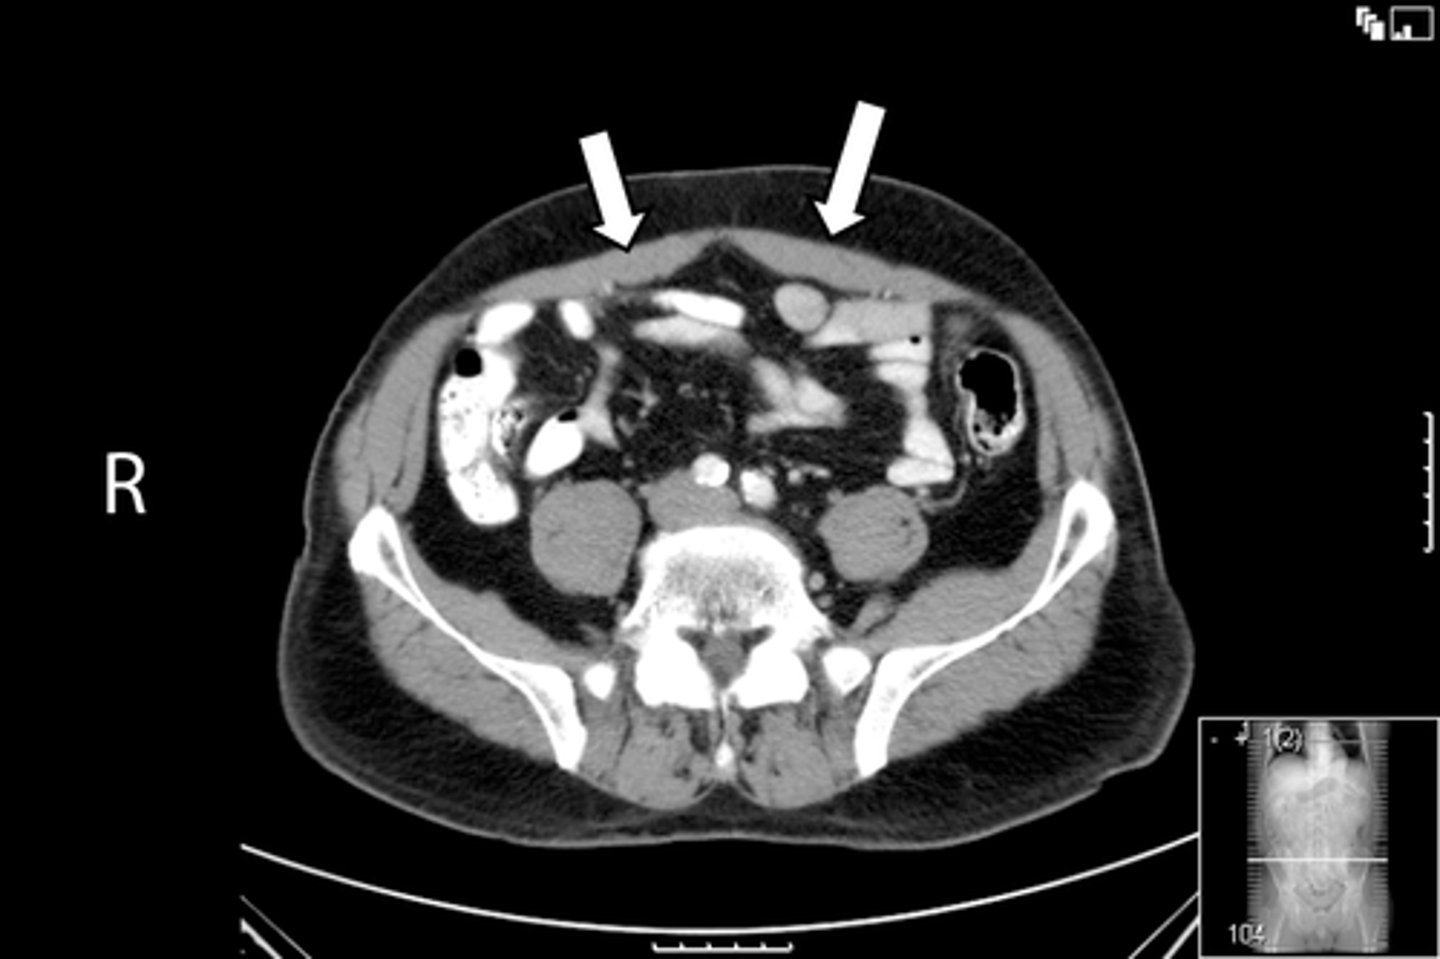

New cards

Axial male pelvis CT

What is the image?

<p>What is the image?</p>

65

Descending colon

What is indicated in the image?

<p>What is indicated in the image?</p>

66

L common iliac artery

67

L gluteus muscle

68

L iliacus muscle

69

L ilium

70

L psoas muscle

71

R common iliac artery

72

R gluteus muscle

73

R iliacus muscle

74

R ilium

75

R psoas muscle

76

R and L rectus abdominis

77